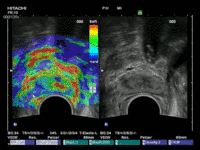

Die Methoden Ultraschall-Elastographie, der farbkodierte Doppler-Ultraschall sowie der kontrastmittelverstärkter Ultraschall und insbesondere die Echtzeit-MRT-Ultraschall-Fusion können helfen, auffällige Gebiete in der Prostata aufzuzeigen. So kann zum Beispiel ein in einer MRT (Magnetresonanztomographie) gefundener suspekter (also auffälliger) Bereich ganz gezielt biopsiert werden und auch zusätzlich noch elastographisch untersucht werden. Dies ist während einer herkömmlichen MRT-Untersuchung nicht möglich.

Eine multimodale Prostataabklärung erlaubt uns, die Prostata mittels modernster Verfahren zu untersuchen. Hierbei kommen verschiedene Untersuchungsmethoden zur Anwendung. Insbesondere die Echtzeitelastographie oder die kontrasmittelunterstützte Untersuchung der Prostata können hierbei wichtige Erkenntnisse über die Beschaffenheit der Prostata beisteuern. Auffällige Areale können in Echtzeit schmerzfrei mit lokaler Betäubung abgeklärt werden. Als Besonderheit können diese modernen Methoden auch mit einer bereits durchgeführten MRT-Untersuchung der Prostata fusioniert werden. Das bedeutet, in einer MRT gefundene auffälligen Areale der Prostata können zusätzlich mit modernsten Ultraschalluntersuchungen kombiniert untersucht werden und dann auch gezielt mittels gezielter Prostatabiopsie abgeklärt werden. Diese Untersuchung ist dann multimodal (zB Elastographie + konventionellem Ultraschall + MRT-Fusion).

Eine multimodale Prostataabklärung erlaubt uns, die Prostata mittels modernster Verfahren zu untersuchen. Hierbei kommen verschiedene Untersuchungsmethoden zur Anwendung. Insbesondere die Echtzeitelastographie oder die kontrasmittelunterstützte Untersuchung der Prostata können hierbei wichtige Erkenntnisse über die Beschaffenheit der Prostata beisteuern. Auffällige Areale können in Echtzeit schmerzfrei mit lokaler Betäubung abgeklärt werden. Als Besonderheit können diese modernen Methoden auch mit einer bereits durchgeführten MRT-Untersuchung der Prostata fusioniert werden. Das bedeutet, in einer MRT gefundene auffälligen Areale der Prostata können zusätzlich mit modernsten Ultraschalluntersuchungen kombiniert untersucht werden und dann auch gezielt mittels gezielter Prostatabiopsie abgeklärt werden. Diese Untersuchung ist dann multimodal (zB Elastographie + konventionellem Ultraschall + MRT-Fusion).

Die Echtzeit-Elastographie ist eine Messung der Elastizität des Prostatagewebes. Dies ist ein bildgebendes Verfahren, mit dem tumorverdächtiges Gewebe in der Prostata mittels verschiedenen Farben auf dem Ultraschallmonitor angezeigt wird. Dabei misst die Ultraschall-Elastographie die Elastizität des Gewebes, also die Härte des Prostatagewebes indem es die Reaktion des Gewebes auf Druck misst. Tumorgewebe ist in der Regel härter als gesundes Gewebe. Die harten tumorverdächtigen Areale werden so aufgespürt und können sofort gezielt biopsiert werden. Die Ultraschall-Elastographie erzielt beim Aufspüren von Tumorbereichen in der Prostata deutlich aussagekräftigere Ergebnisse als der herkömmliche Ultraschall.

Zunächst einmal werden die bereits durchgeführten und von Ihnen mitgebrachten MRT-Bilder (1,5T-3T, mit/ohne rektale Spule, DICOM-Format) in unser Gerät eingelesen. Anschließend werden die suspekten Areale und die Organgrenzen der Prostata in der MRT-Bildgebung markiert. Nun beginnt der praktische Teil: In angenehmer Seitenlage wird über einen modernen transrektalen Ultraschall die Prostata aufgesucht und anhand der Anatomie der Prostata mit dem MRT Bild fusioniert. Der Untersucher sieht nun auf der linken Seite des Flachbildschirmes des Ultraschallgerätes das Original-MRT-Bild mitsamt des Markierungen und auf der korrespondierenden rechten Seite die Live Ultraschallbilder in denen die Markierungen der MRT-Untersuchung zu sehen sind. Die auffälligen Areale können nun einer Elastographie oder einer Kontrastmittel-Untersuchung unterzogen werden um den Grad der Auffälligkeit zu bestimmen. Auf Wunsch können auch jetzt gleich die Biopsien durchgeführt werden.